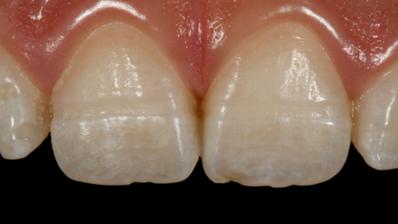

Se puede presentar Amelogénesis imperfecta, Hipomineralización molar incisivo, Hipoplasia del esmalte y por supuesto Caries dental

Se considera que los pacientes con

Celíaca tienen mayor riesgo de desarrollar defectos del esmalte (50%)

Este es un defecto cuantitativo del esmalte, es decir, existe buena mineralización pero cantidad disminuida de este tejido en la zona del defecto. Existe pérdida de la continuidad del tejido, con posible exposicion de dentina y se presenta con bordes definidos, redondeados y generalmente son de color blanco o crema

La diferencia con la Hipomineralización molar incisivo está en su estructura, origen y color No tiende a presentar colores tan intensos y su aparición es aleatoria e idiopática en la mayoría de los casos Se le debe prestar mucha atención ya que puede desencadenar situaciones graves por decisiones incorrectas en los tratamientos, mal uso de los materiales odontólogicos e identificación tardía.